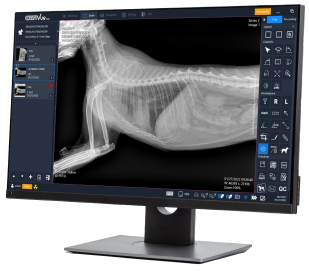

Powered by ExamVue™ Acquisition Software

DynaVue™ Duo is powered by

Specialized Tools for Veterinarians

🔹Axial Angle

🔹Clock Face

🔹Clock Face (Lat View)

🔹Clock Face (VD View)

🔹Cross Angle

🔹Liver Size

🔹Middle Angle

🔹Norberg Angle

🔹Percent Coverage

🔹Spine Label

🔹TPA

🔹Vertical Discrepancy

🔹VHS

🔹VLAS

🔹Vertebral Heart Score

🔹Norberg Hip Analysis

🔹TPLO Analysis

🔹TTA Analysis